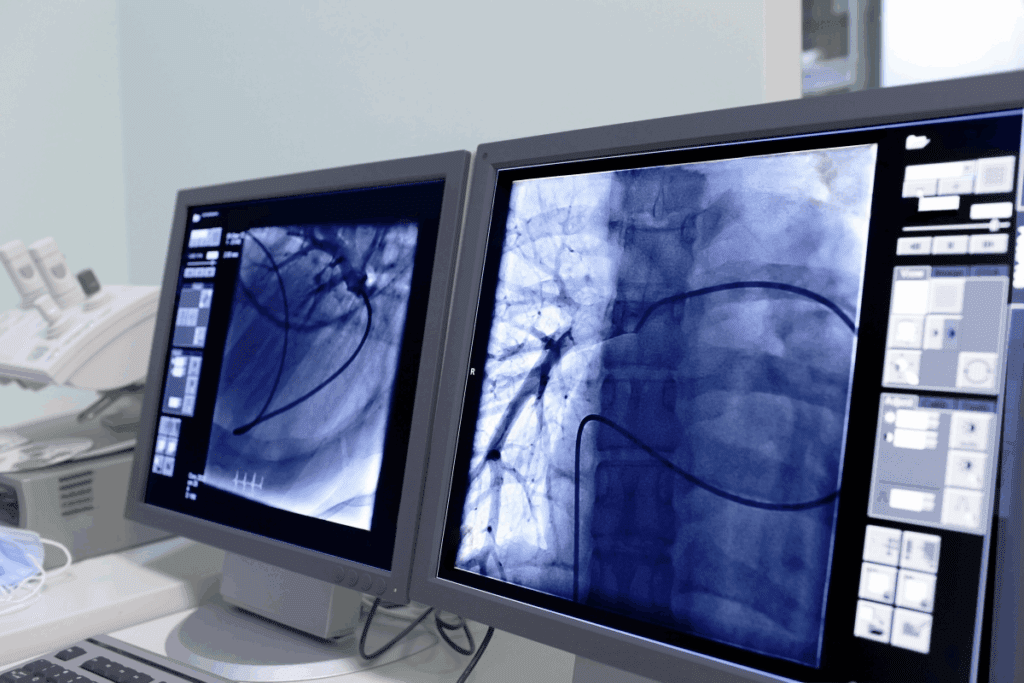

Interventional radiologists are key in diagnosing and treating complex health issues. They use advanced imaging to do minimally invasive procedures. This makes treatments safer and less invasive than traditional surgery.

Interventional radiologists use imaging to find and treat many health problems. This includes heart diseases, cancers, and stomach issues. They do things like angioplasty and tumor removal.

They use X-rays, CT scans, MRI, and ultrasound to guide their work. This makes treatments more precise and effective.

Thanks to these imaging tools, interventional radiologists can offer targeted treatments. These treatments are safer, have shorter recovery times, and cause less pain than surgery.